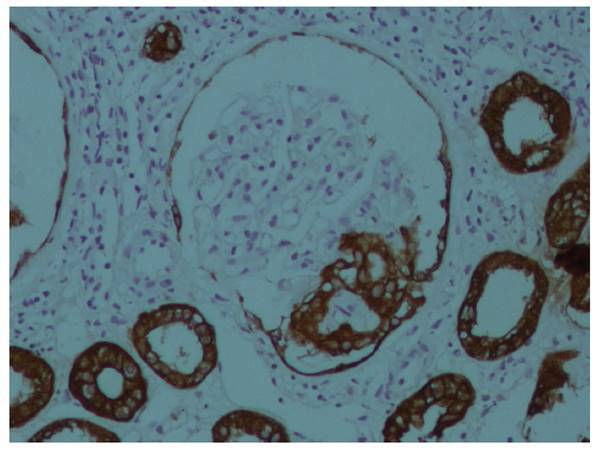

Se realizó biopsia renal cuyo informe fue: “GEFS, variante Colapsante, 17 glomérulos, ninguno globalmente esclerosado. Glomérulos aumentados de tamaño, expansión e hipercelularidad mesangial, rigidez segmentaria de asas capilares, dos con colapso capilar, hipertrofia e hiperplasia de podocitos. Túbulos con degeneración turbia y atrofia focal. Intersticio con LMN (1+) y fibrosis mínima. Inmunohistoquímica: Panqueratina (+), CD68 (+), Vimentina (-), en podocitos. Inmunofluorescencia: IgG (-), IgM (-), IgA (-), C3 (-), C1q (-), Kappa (-) y Lambda (-)”. (Figuras 1 y 2).

Figura 2 Inmunohistoquímica 400X: Panqueratina (+) en zona de colapso capilar y en túbulos renales, que presentan degeneración turbia.

Purva Sharma 9 en una serie de casos, reportó la mitad de los pacientes con hallazgo histológico de injuria renal aguda con compromiso tubular, y sólo uno de ellos con glomerulopatía colapsante, sin positividad de la inmunohistoquímica. En el presente caso, se evidenció la prueba de panqueratina positiva; aunque el estudio de Purva Sharma presentó hallazgos en microscopía electrónica, lo que no se pudo concretar en nuestro caso.